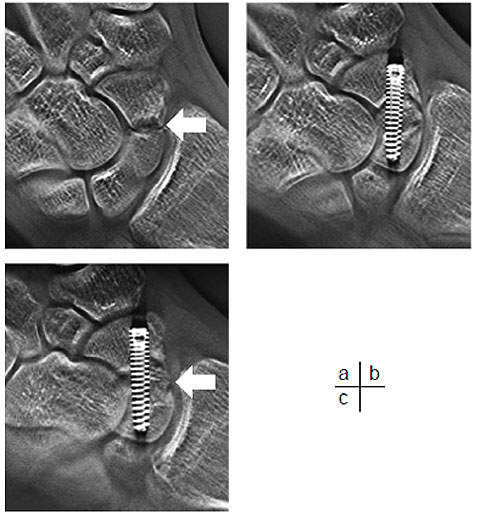

Case 4 – 15-year-old male: injured right hand in a fall from a bicycle and visited our hospital one month later, after diagnosis of fracture of the scaphoid bone at another hospital. Tomosynthesis performed on arrival at the hospital confirmed a bone defect in the scaphoid waist. A bone graft with screw fixation and cast immobilization was performed two months after the injury. The fracture line in the scaphoid bone has become indistinct in the tomosynthesis image taken in the 16th week. This is assumed to result from progress of bone union (Fig. 13).